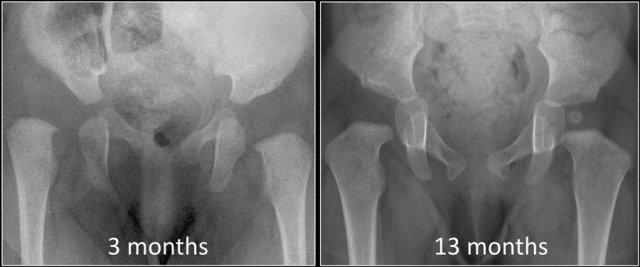

Có những trẻ được sinh ra với khớp háng bình thường nhưng sau đó phát triển thành loạn sản (hình).

Trong trường hợp này, trẻ mắc một rối loạn thần kinh cơ khiến hông bị loạn sản và trật khớp.

Mặt khác, có những trẻ em sinh ra với chứng loạn sản khớp háng tự khỏi hoặc sau khi điều trị tương đối đơn giản, ví dụ như đai Pavlik (hình).

Vì vậy, chúng ta phải nhận thức rằng DDH là một bệnh lý động và không phải lúc nào cũng hiện diện ngay từ khi sinh ra như tên gọi loạn sản háng bẩm sinh đã gợi ý.

Điều trị sẽ dễ dàng hơn và các biến chứng ít có khả năng xảy ra hơn khi DDH được chẩn đoán sớm.

Trong trường hợp này, ở tháng thứ 13, dấu hiệu duy nhất còn lại của loạn sản trước đây là sự chậm cốt hóa của chỏm xương đùi.